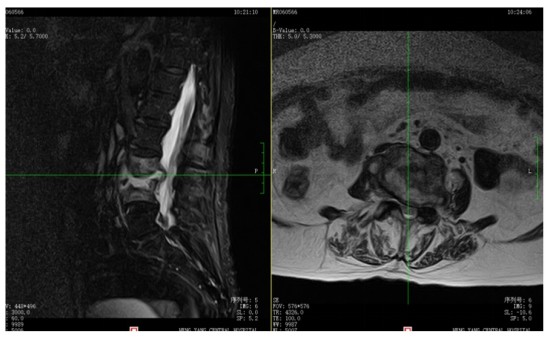

為解決老人病痛,脊柱外科錢軍博士團(tuán)隊(duì)對其進(jìn)行了詳細(xì)的查體以及全面細(xì)致的評估,診斷為L3、4脊柱結(jié)核伴病理性骨折、椎旁膿腫,患者腰部疼痛癥狀逐漸加重,病灶已經(jīng)壓迫神經(jīng)引起了截癱。